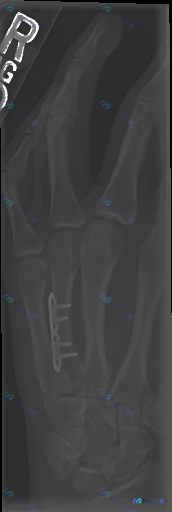

整理到一份左手拇指的术后影像资料,先把客观的影像观察结果放出来,大家第一眼会怎么解读? 影像学客观发现: - 左拇指近节指骨内可见高密度金属内固定钉,沿指骨长轴走行 - 内固定周围骨质结构中,未见明显透亮骨折线,皮质轮廓基本连续 - 掌指关节、指间关节对位关系尚可,关节间隙清晰 - 软组织密度未见明...